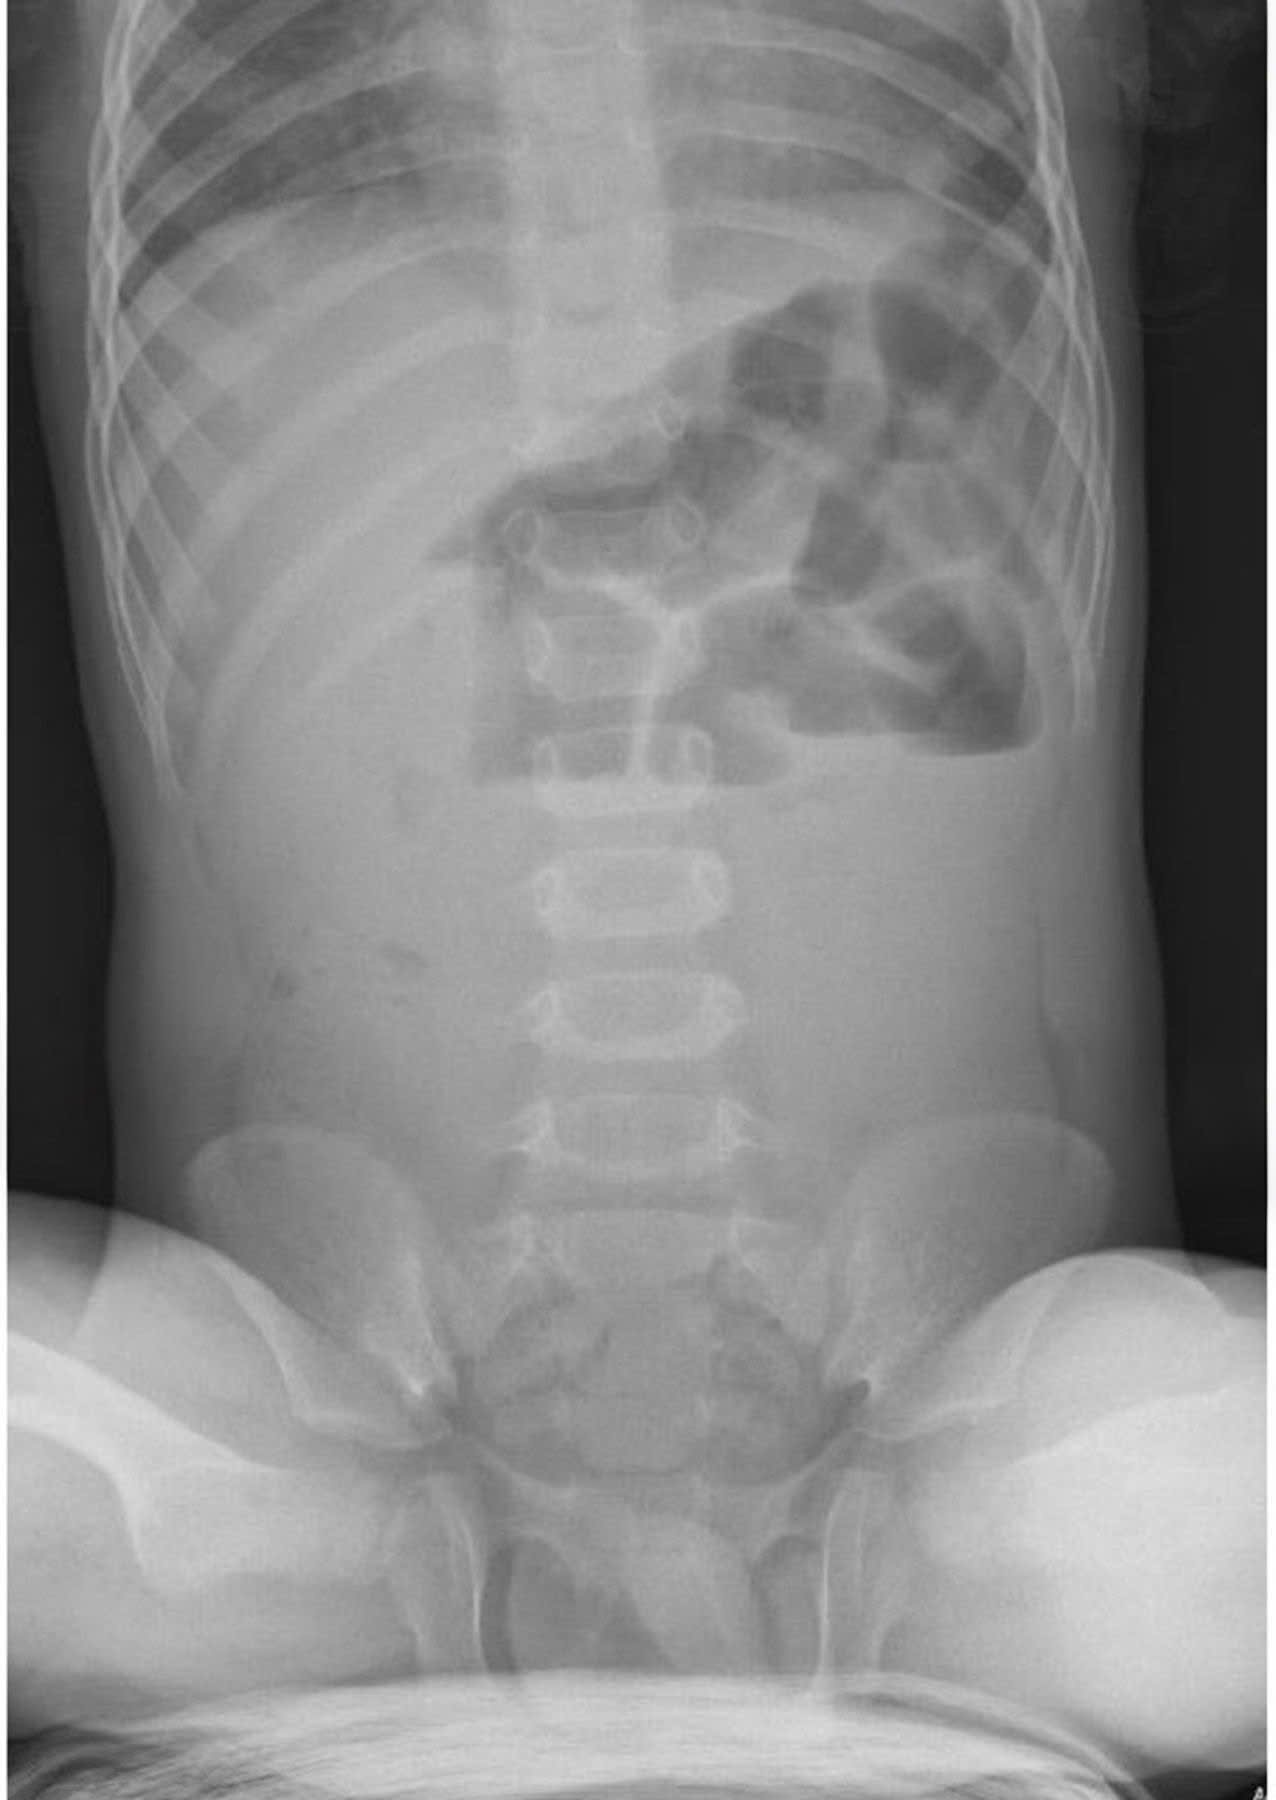

- Bụng Chướng To: Bụng căng cứng, sưng phồng.

Trong nhiều trường hợp, tắc ruột do bã thức ăn có thể điều trị nội khoa bằng thuốc nhuận tràng, thụt tháo… Tuy nhiên, khi tình trạng tắc nghẽn nghiêm trọng, gây biến chứng nguy hiểm như hoại tử ruột, thủng ruột…, can thiệp ngoại khoa là giải pháp tối ưu để cứu sống trẻ.